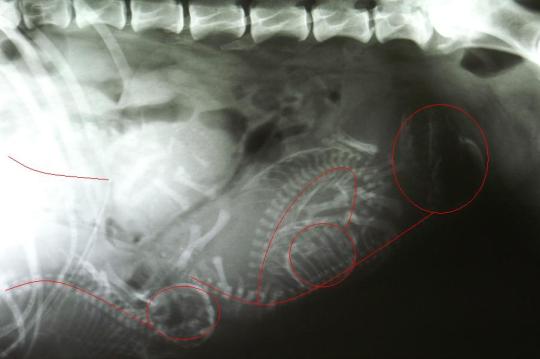

Eine Röntgenaufnahme zeigt, dass noch vier weitere Welpen darauf warten, geboren zu werden. Bei einem Fötus ist ersichtlich, dass der Hals um 180° nach hinten abgebogen ist.